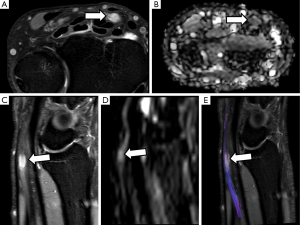

Assessment of the median nerve for the study of carpal tunnel syndrome has classically been a challenge for the radiologist. Numerous studies have demonstrated with proper results the utility of ultrasound (59) and conventional MRI studies to evaluate median nerve at flexor retinaculum (60). However, in some patients there is not apparent cause of median nerve compression despite the presence of clinical symptoms. It is in this group of patients where neurographic techniques based on DWI and DTI are showing promising results, not only in diagnosis but also in monitoring the results of surgical treatment.Median nerve has been one of the first PN deeply studied by DTI. Several studies have detailed the technical optimizations for DTN comparing healthy controls with patients with carpal tunnel syndrome (22,61,62). These studies have shown a reduction in FA values in patients with symptoms consistent with carpal tunnel syndrome, suggesting that due to compression, the median nerve loses its physiological anisotropic structure as the extracellular space increases, Also, DTN can detect long-standing neural changes (63). An increase of ADC values is also depicted due to the presence of edema (64).

The decrease of FA values has demonstrated to be more sensitive to changes in median nerve than ADC, especially at the distal carpus, after its path under the flexor retinaculum, where the most significant variation with regard to healthy volunteers is detected (63) (Figure 12). Other parameters such as MD, RD and AD have also been tested with promising results for carpal tunnel syndrome evaluation and with proper correlation with electrophysiological studies (5). Several cut-off points for FA values have been proposed for carpal tunnel syndrome diagnosis (65). However, differences due to technical factors such as acquisition protocols, magnet field strength (1.5 vs. 3.0 T), threshold FA values, reconstruction algorithms and even patient’s age can act as potential bias and limit reproducibility (66). So, until a greater degree of standardization is achieved and based on the existing scientific literature, it seems reasonable to perform measures of the different parameters at least within carpal tunnel as well as at its proximal and distal segments.

In patients undergoing surgical decompression of the median nerve, DTN has also been used for assessment of changes in FA before and after the intervention. It has been shown that there is a progressive increase of FA values within the first 6 weeks to 6 months after surgery in patients with clinical improvement. This increase was identified in both the proximal and distal segment of the median nerve at the wrist (67).